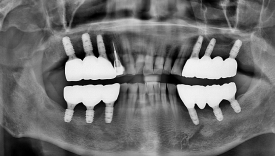

<혈전제 복용 환자로 복용약 중단을 최소화하고

의식하진정요법을 통해 위/아래 두 번만에 수술 후 보철 완료 사례>

저희는 의식하진정요법을 활용해 한 번의 수술로 많은 임플란트를 심을 수 있어 환자의 부담을 줄일 수 있는데요.

의식하진정요법은 잠을 자는 것처럼 긴장을 완화하고 편안한 상태에서 받을 수 있고, 이는 회복에도 긍정적인 영향을 줍니다.